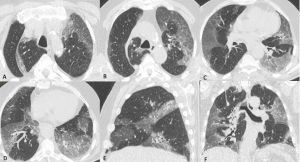

Figura 12: Donna di 70 anni affetta da tumore al polmone in trattamento con un inibitore della tirosin-chinasi. Trascorsi 15 giorni dall’inizio della terapia la paziente lamenta sempre maggiori difficoltà respiratorie e tosse. Alla TC di controllo (scansioni assiali A-B-C-D) si rileva "vetro smerigliato" diffuso in entrambi i polmoni ed ispessimento liscio di alcuni setti interlobulari. Si giunge alla diagnosi di pneumpatia indotta da farmaci dopo aver escluso le ipotesi di edema cardiogeno e di infezione polmonare.

Figura 13: Uomo di 45 anni giunge in Pronto Soccorso per IRA e grave anemizzazione. La TCAR eseguita all’ingresso (scansioni assiali A-B-C e ricostruzione MPR sul piano coronale D) mostra la presenza in entrambi i polmoni di multiple aree di aumentata densità con aspetto in parte a "vetro smerigliato" ed in parte consolidativo con broncogramma aereo nel contesto e distribuzione simmetrica, prevalente in sede perilare con risparmio delle zone subpleuriche. In considerazione della clinica e della distribuzione delle lesioni l’ipotesi diagnostica formulata (in seguito confermata dal BAL) è quella di emorragia alveolare diffusa.

Figura 14: Paziente di sesso femminile, 75 anni, con storia di interstiziopatia polmonare inquadrata come UIP probabile dal 2018. La paziente giunge al Pronto Soccorso per repentino e grave peggioramento della funzionalità respiratoria. Le immagini TCAR assiali (A-B) documentano la presenza in entrambi i polmoni di multiple aree a “vetro smerigliato” con distribuzione diffusa. Dopo aver escluso le ipotesi di edema cardiogeno e di infezione polmonare viene posta diagnosi di esacerbazione di fibrosi polmonare idiopatica.